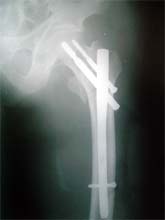

股骨粗隆间骨折,严重移位。            采用闭合复位伽马钉内固定。